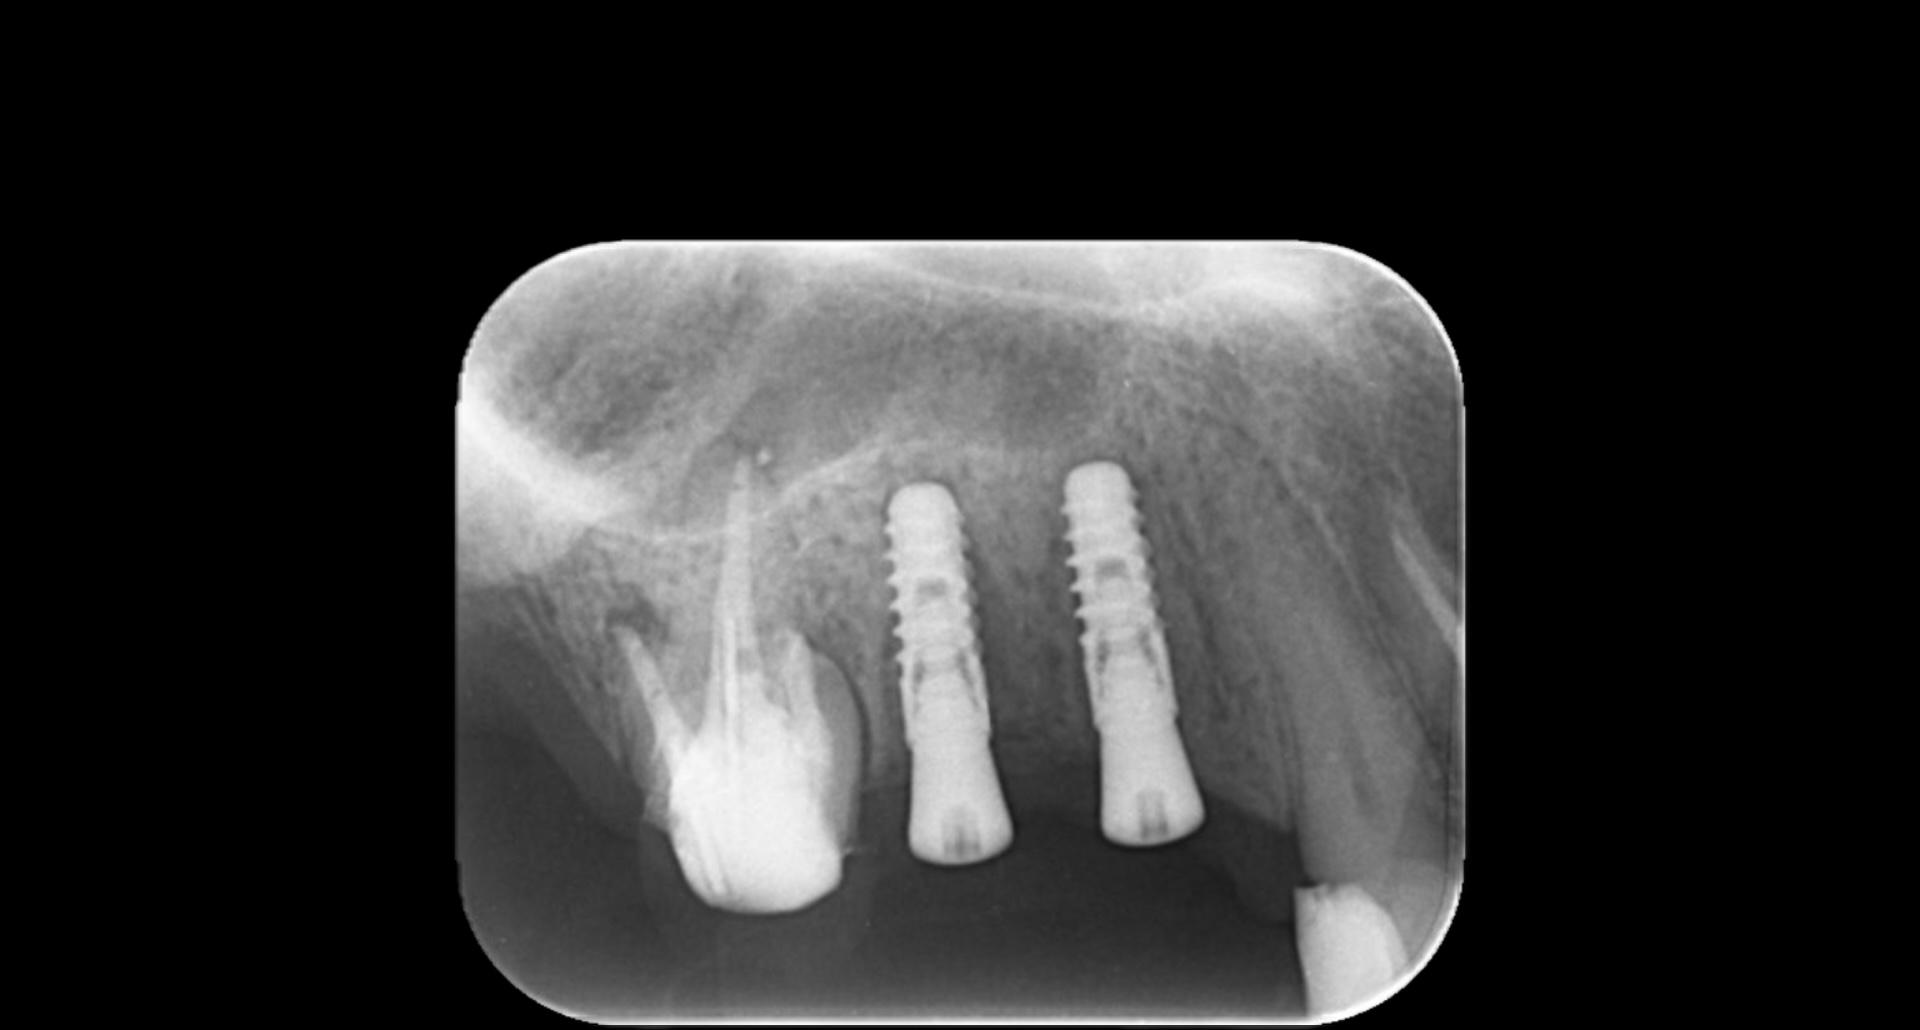

上のガイドを使った症例はこのように小臼歯が作りやすい位置に正確にインプラント埋入をできました。

骨幅が細いケースで埋入位置がずれると、骨が裂開してしまうケースですが、裂開無く、骨増生もせず、最小限の侵襲(MI)でインプラント埋入を無事終えております。